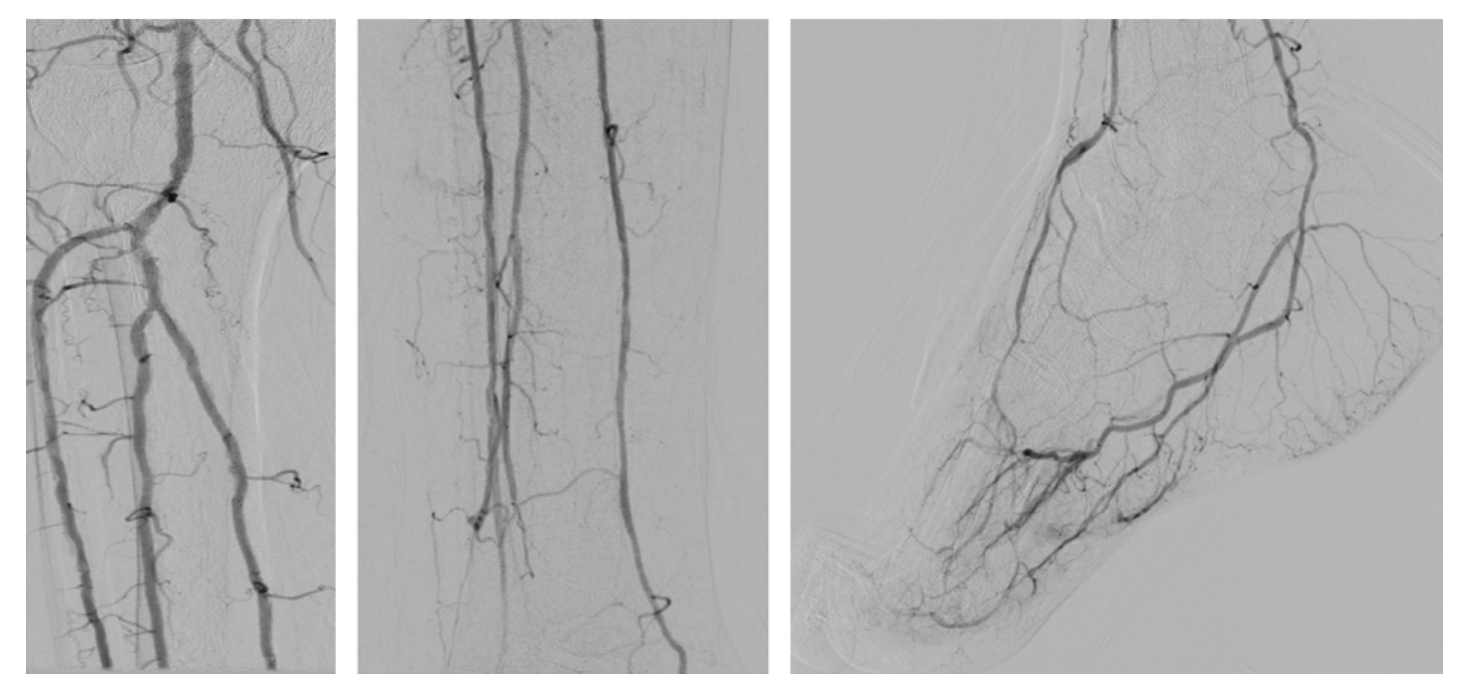

The patient had a right transradial aortogram with selective right leg angiogram. His angiogram revealed adequate inflow with patent aorto-iliac, common femoral, superficial femoral, profunda, and popliteal vessels. Distally he had a chronically occluded (CTO) right anterior tibial (AT) with a hibernating dorsalis pedis artery (DP) that faintly filled from a peroneal (PER) collateral, 90% tibial peroneal trunk (TPT) stenosis, multiple 75% lesions in the proximal and mid posterior tibial artery (PT), and a patent lateral plantar artery (LP) (Figure 1).

Anticipating a high risk of complications related to transfemoral access, we decided to proceed with a TAMI approach utilizing transradial guidance. A 4 to 5 French (Fr) Glidesheath Slender sheath (Terumo) was inserted in the right radial artery for visualization of the proximal vessels. We placed a 2.9 Fr Cook pedal sheath (Cook Medical) in the AT and advanced an .018-inch CXI support catheter (Cook Medical) over an .018-inch Command ST wire (Abbott Vascular). The CXI catheter and wire were advanced through the course of the ATA intraluminally, except for the ostium of the ATA, where the wire entered a subintimal space. Thereafter, we gained access in the right PT with a 4 to 5 Fr Glidesheath Slender sheath to serve as an antegrade access to cross the ATA CTO (Figure 2). An .018-inch CXI support catheter was telescoped within a 4 Fr Berenstein catheter (Boston Scientific) with an .018-inch Command wire advanced into the proximal AT (Figure 3). The antegrade equipment was advanced into the distal AT. The retrograde CXI catheter was pulled back in the distal AT, where the antegrade wire was inserted for externalization. Subsequently, the antegrade CXI catheter was externalized through the retrograde 2.9 Fr sheath placed in the distal AT (Figure 4). The .018-inch Command wire was exchanged for an .014-inch ViperWire (Cardiovascular Systems, Inc. [CSI]) guidewire to perform atherectomy using a 1.5 mm classic crown Diamondback 360 catheter (CSI) in the PT, TPT, and AT (Figure 5). Thereafter, based on extravascular ultrasound (EVUS) measurements, we performed balloon angioplasty of the proximal DP, AT, and PT with a 3.5 x 300 mm Ultraverse balloon (BD), and TPT with a 4.0- x 60-mm Lutonix drug-coated balloon (BD) with an excellent result (Figure 6).